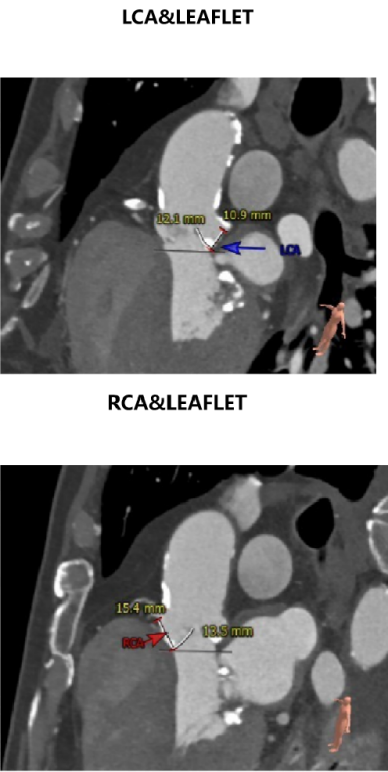

②患者左冠开口高度约12.2mm,近端开口处可见钙化,左冠窦瓣叶长度大于左冠开口到瓣叶根部距离,结合瓦氏窦宽度预估,左冠稍有封堵风险;

主动脉瓣瓣环周长70.8mm,平均周长径 22.6mm,SOV:31.9mm*28.0mm*29.0mm,瓣叶增厚,瓣上见明显钙化,瓣环水平夹角48°,左冠高度12.2mm,右冠高度15.5mm,HU850钙化积分704mm³。